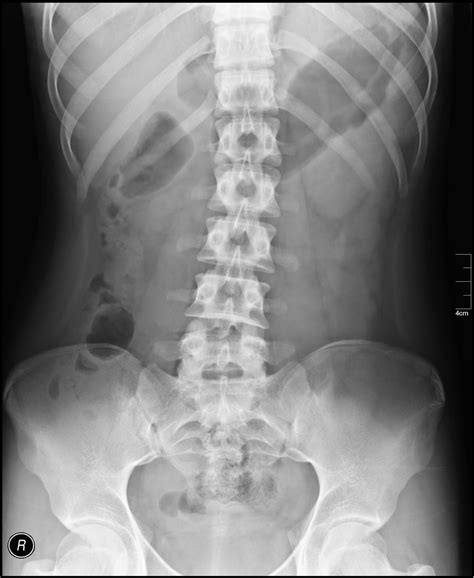

Common Findings in a Normal Abdominal X Ray

A Normal Abdominal X Ray typically reveals the following structures and patterns:

• Gas patterns in the stomach and intestines

• Clear outlines of the liver, spleen, and kidneys

• No signs of obstruction or perforation

• No evidence of foreign bodies

These findings indicate that the abdominal organs are functioning normally and there are no immediate concerns.